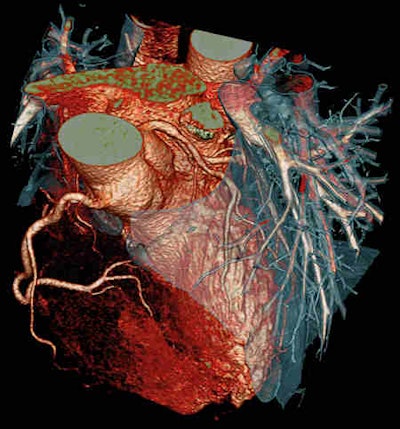

Looking at an occlusion with angiography, you have no idea about what is going on behind that occlusion, but CT can visualize the amount of plaque and also the coronary lumen, according to Achenbach. With a high negative predictive value consistently ranging between 98% and 99% in different studies, CT allows cardiologists to confidently rule out stenosis, giving it a high prognostic value. The modality has a close-to-zero event rate after ruling out stenosis, allowing 84% of patients to be sent home without a single recorded cardiac event among this population over the next 30 days.

CT has lower spatial resolution than invasive angiography, such that severe calcifications can become a problem. Temporal limitations can make motion problematic, requiring a breath-hold and even still producing artifacts within the image due to natural heart movement.

The angiography image may seem misty and blurred, but it shows the whole picture, with a synthesis of all layers of the heart immediately available, Meier commented. It may be old and not fancy, but angiography provides information CT cannot give, such as hemodynamics and flow patterns, and pressure grades can be measured with catheterization, he said.